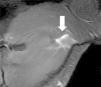

Se caracteriza por un incremento en la intensidad de señal del músculo, el cual puede estar asociado con un acortamiento del espacio entre el isquion y el trocánter menor (fig. 8). El dolor se produce por la irritación del nervio ciático, cuya ubicación es adyacente al cuadrado femoral, en relación posterior.

Desgarro del músculo cuadrado crural y síndrome isquiofemoral derecho. La secuencia ponderada en STIR, plano axial, revela un edema interfibrilar a nivel del músculo cuadrado crural (flecha). También se visualiza un ligero acortamiento del espacio entre la tuberosidad isquiática y el trocánter menor en el lado derecho, en comparación con el contralateral.